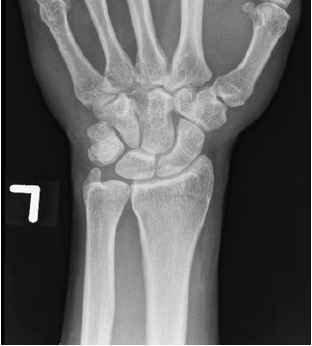

Avascular Necrosis of the Hamate Treated with a 4–5 Extensor Compartmental Artery Graft: A Case Report and Literature Review

Mauz Asghar , Jonathan Persitz , Norah Matthies Andrea Chan , Ryan Paul

………………………………p.223-230